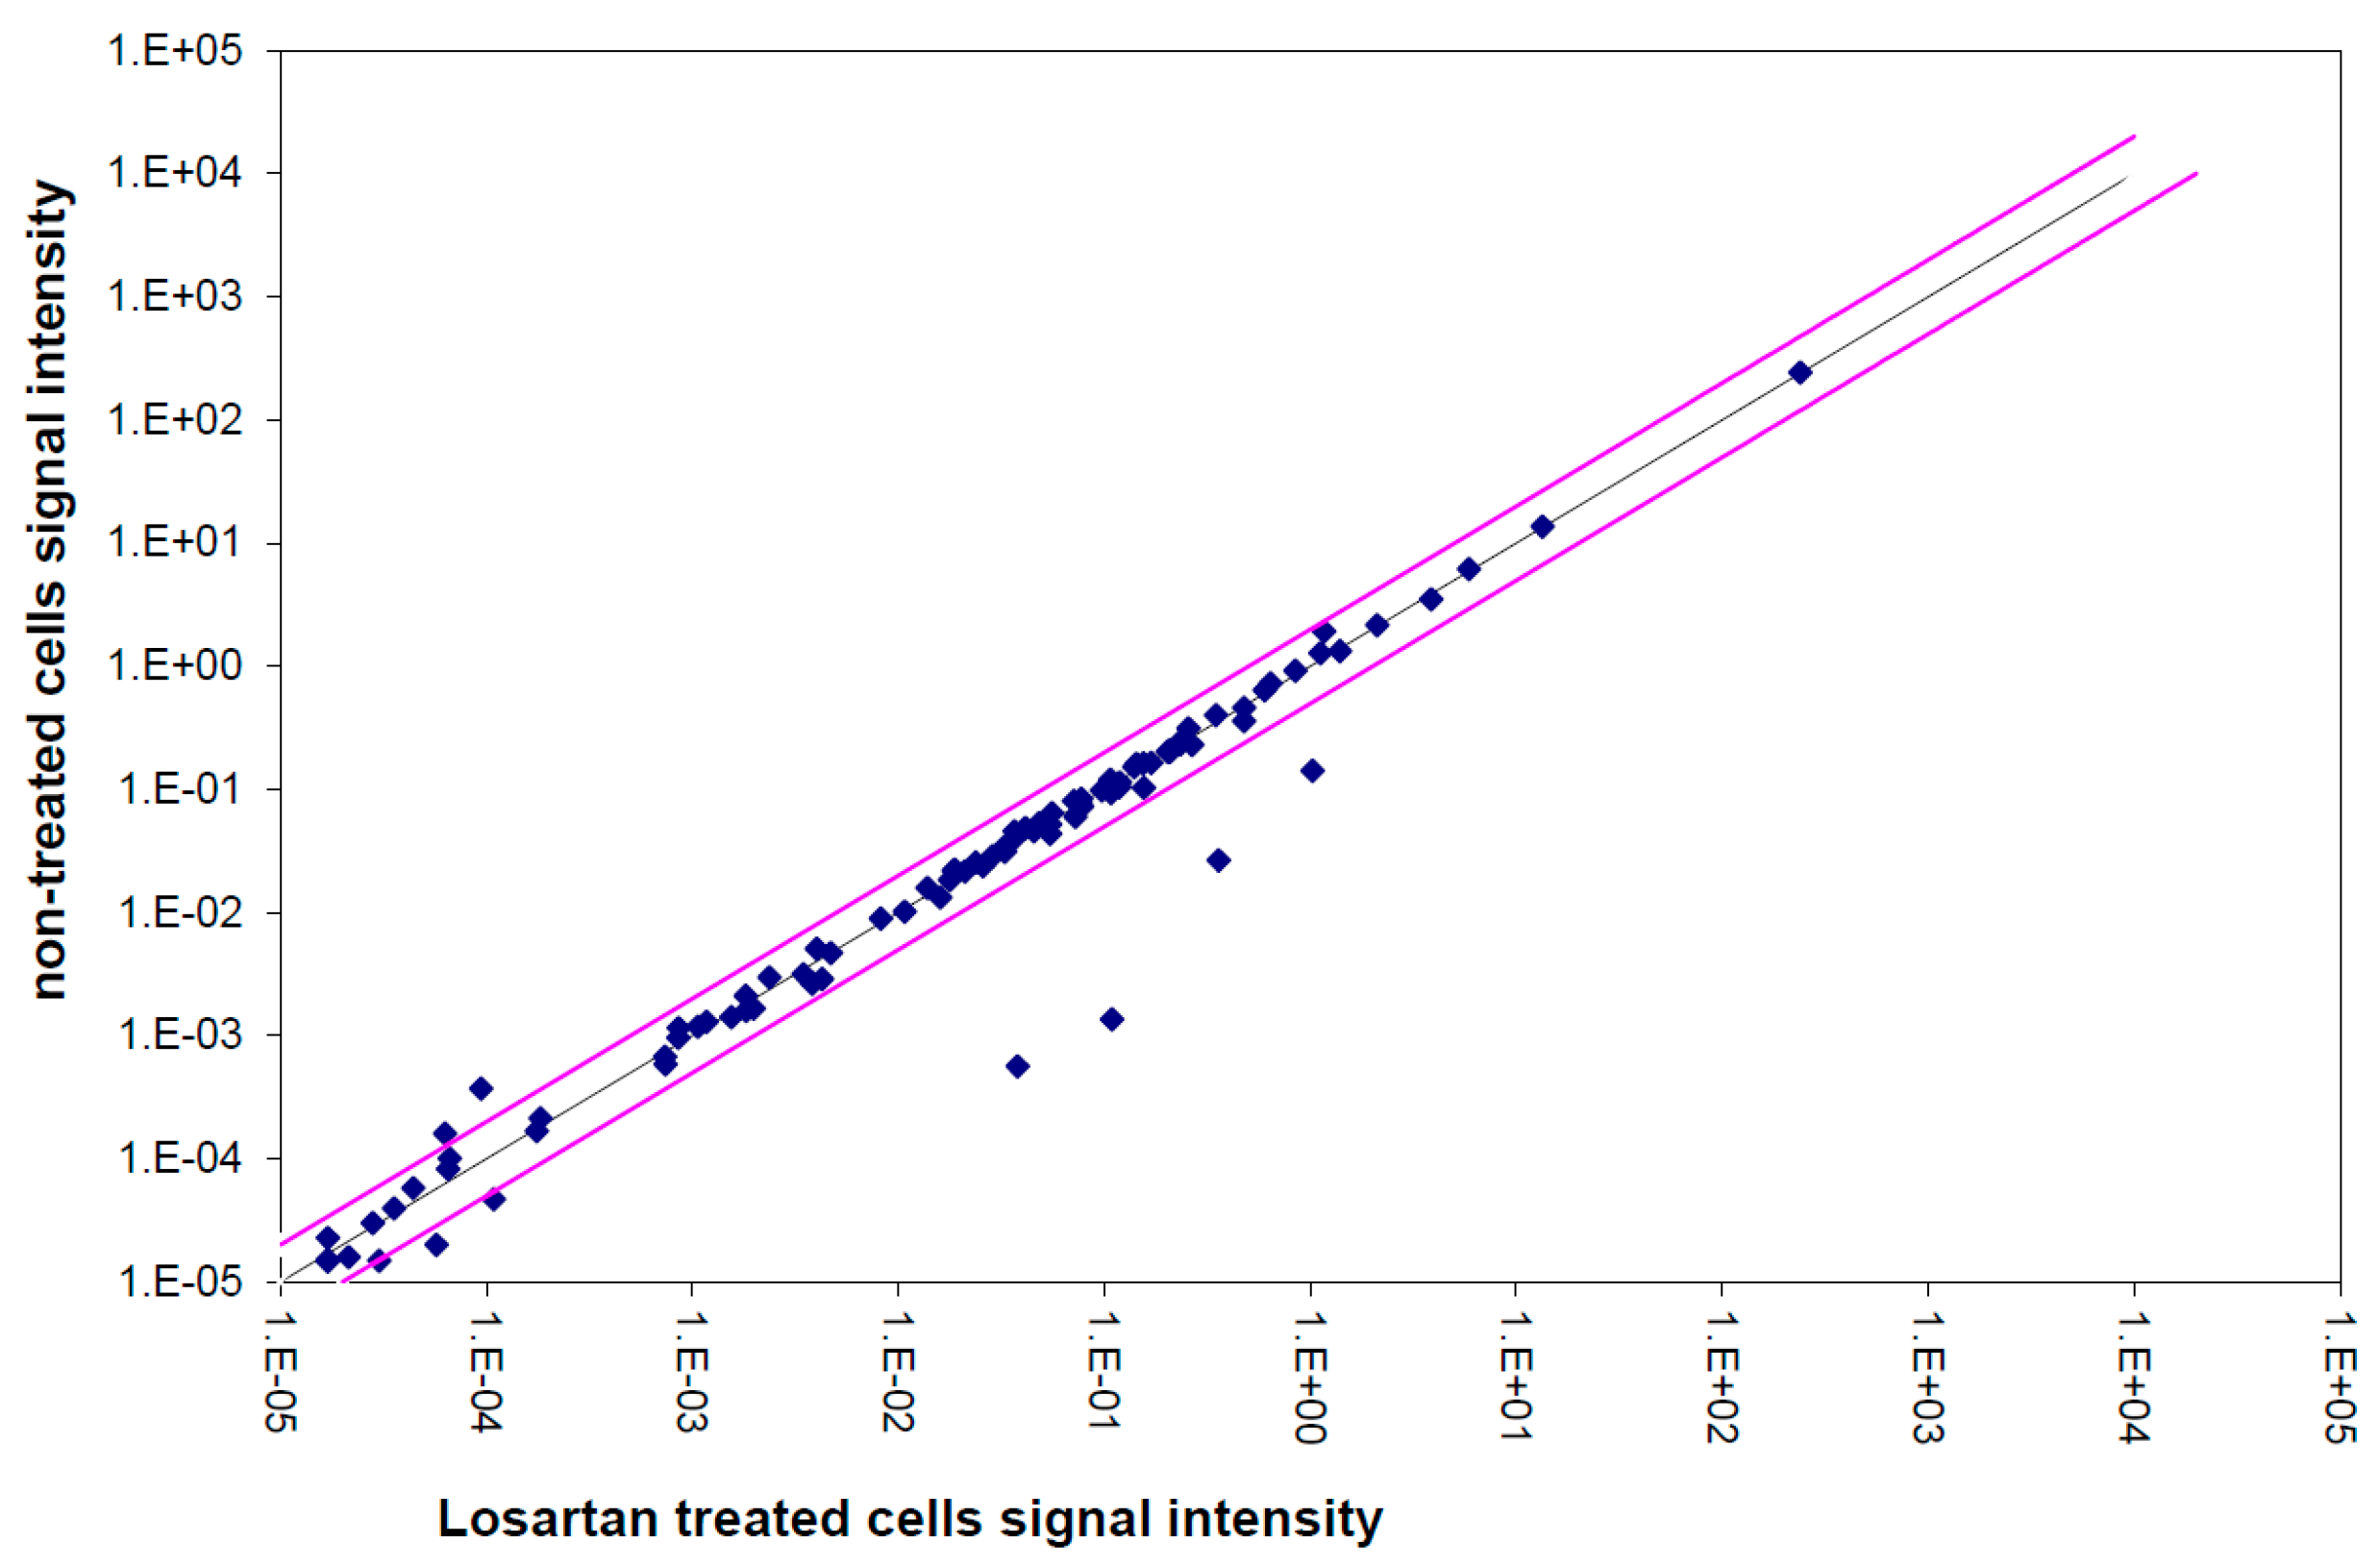

3.5. Gene Expression Analysis of the TGFβ Pathway

4. Discussion